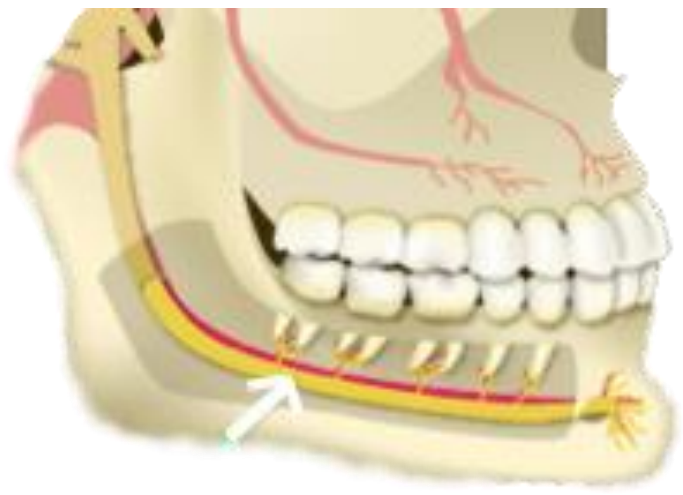

Observe a imagem abaixo:

Assinale a alternativa que apresenta o nome do nervo apontado pela seta: